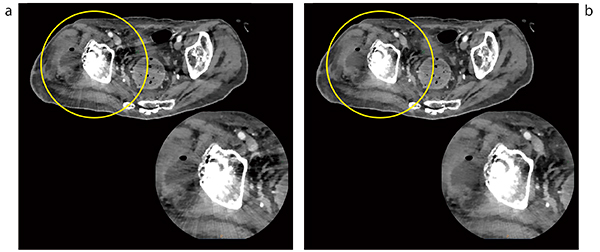

IMR Platinumは,金属アーチファクト低減アルゴリズム“O-MAR”とも併用可能である。これにより,画像に必要な分解能を保ちつつ,ノイズはIMR Platinumで,体内に留置された金属から発生するアーチファクトはO-MARで低減した画像を提供可能である(図3)。

図3 IMR Platinum臨床画像のO-MAR オン/オフ比較

a:O-MARオフ b:O-MARオン

bでは金属アーチファクトに隠れていた囊胞(○)が観察できる。